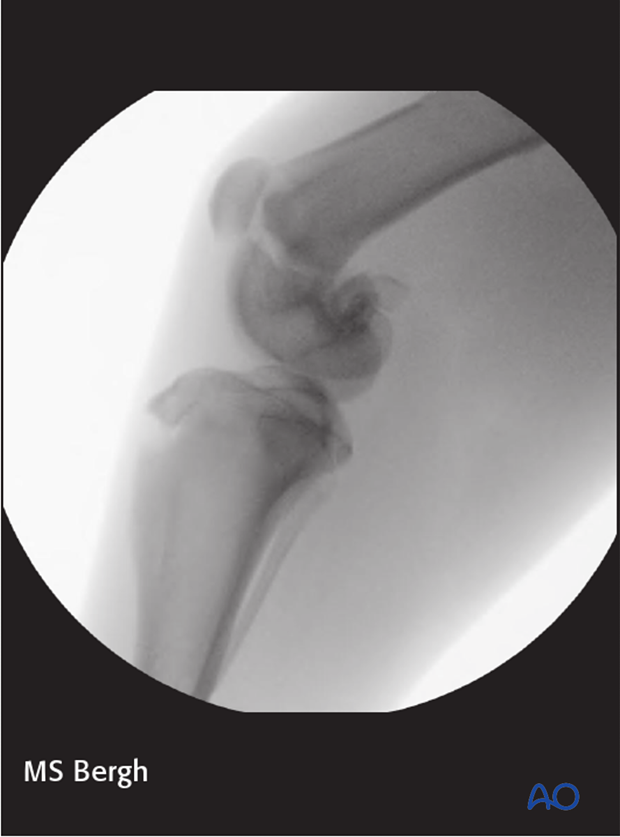

Fluoroscopy or intraoperative radiography is used to ensure appropriate reduction with this approach.